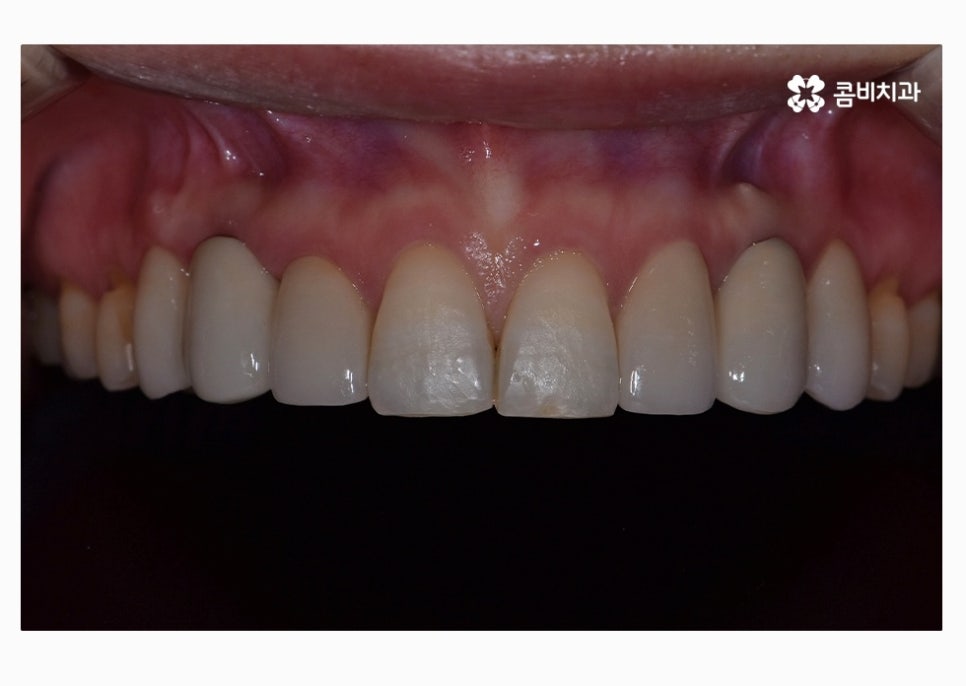

치아교정으로 치열을 가지런하게 하고

30대임플란트 식립까지 잘 마친 상태이며

식립 후에는 골 유착이 튼튼하게 이뤄지는지 기다린 후

주변 치아의 색과 모양에 맞는 보철물을 결합하여

마무리가 된다고 할 수 있어요.

앞니의 경우 심미적으로 중요하기 때문에 임플란트

치료에 있어서 식립 각도부터 보철물의 모양, 색 등

정확해야 하고 연세가 많은 분들의 경우에는